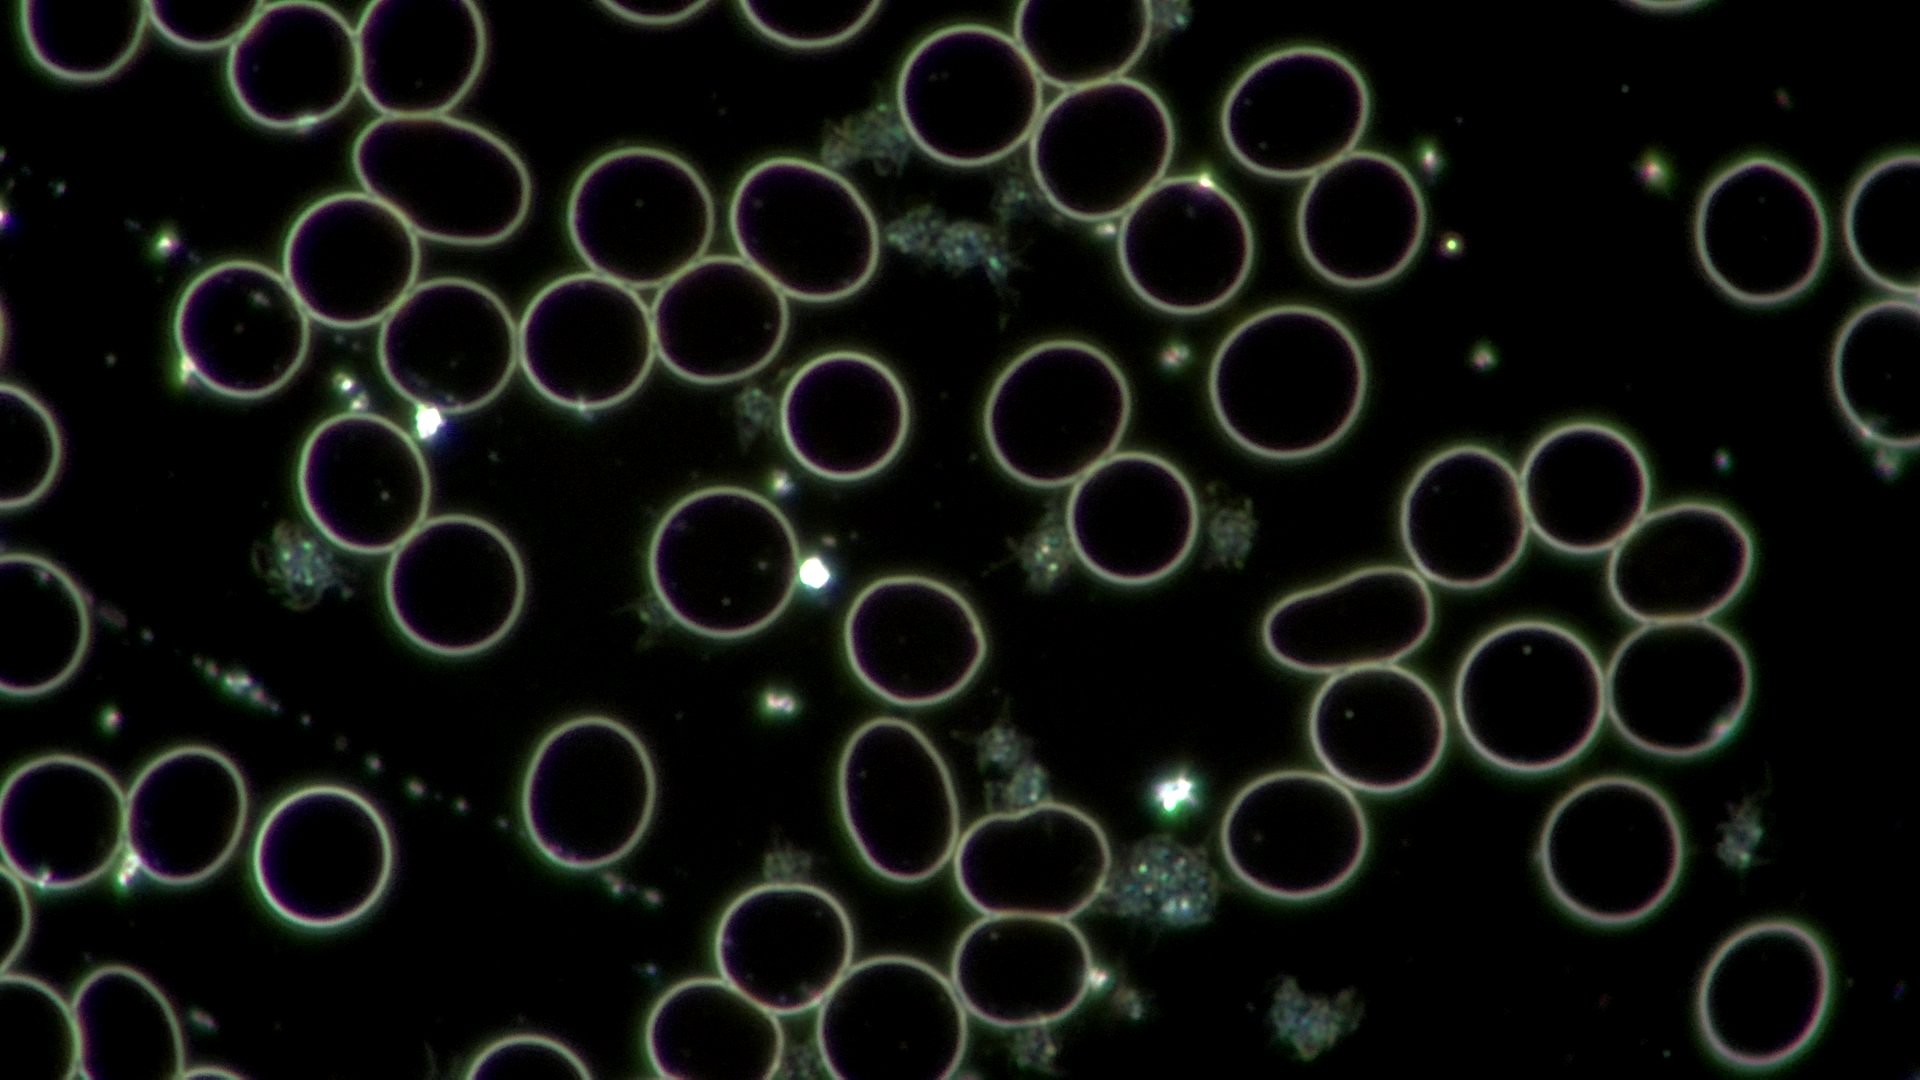

After 15 minutes of breathwork, her blood showed significant improvements - cells could move freely, and stress had been eliminated. Through her breath, she has not only calmed her mind and changed her emotional state, but she also shifted her biology and the health of her body.

She, yes, shifted her emotional state, going from feeling stressed, frustrated (maybe even angry), and overwhelmed with all the racing thoughts to leaving the experience calm, deeply grounded, and her mind at peace.